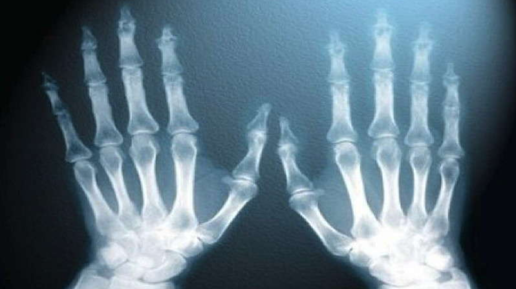

Космонавтов много, но Гагарин всегда будет особенным. Ведь он был первым. То же самое и у ученых. Нобелевская премия по физике вручалась уже множеству выдающихся гигантов науки. Но первым в этом ряду навсегда останется Вильгельм Конрад Рентген. И по праву. 8 ноября 1895 года в лаборатории сорокадевятилетнего Рентгена произошло событие, которое в дальнейшем перевернуло науку. А казалось бы, пустяк. Ученый занимался исследованием электрического разряда в вакуумных стеклянных трубках. В тот день он порядком устал и решил уйти домой пораньше...

Современная лучевая диагностика имеет в своем арсенале несколько абсолютно гениальных методов. Более того, эти методы, вернее, принципы получения изображения, высоко признаны во всем мире. А ведь мало кто знает, что никто иные как нобелевские лауреаты-физики положили начало эре визуализации внутренних органов и целой эпохе сотрудничества физики и медицины. Один из таких гениев, как это часто бывает, сделал свое открытие совершенно случайно. История о забывчивом, но наблюдательном физике Рентгене...